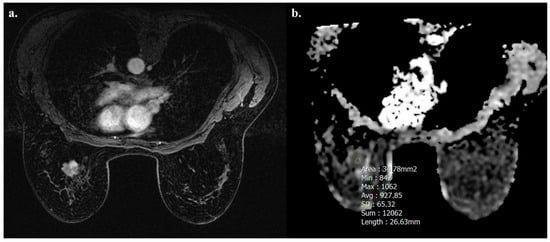

Tumors with high TIL levels also showed more frequently homogeneous enhancement compared to those with low TIL levels (31/54 [57.4%] vs. 17/91 [18.7%], p < 0.001) (Figure 3 and Figure 4).

Figure 4.

A 52-year-old woman with NST BC subtype Luminal B with low TIL levels (3%) in the left breast. Axial T1-weighted contrast-enhanced MR image shows heterogeneously enhanced mass (a), and hypointensity on ADC map (0.927 × 10−3 mm2 s−1), as showed by the circle (b).